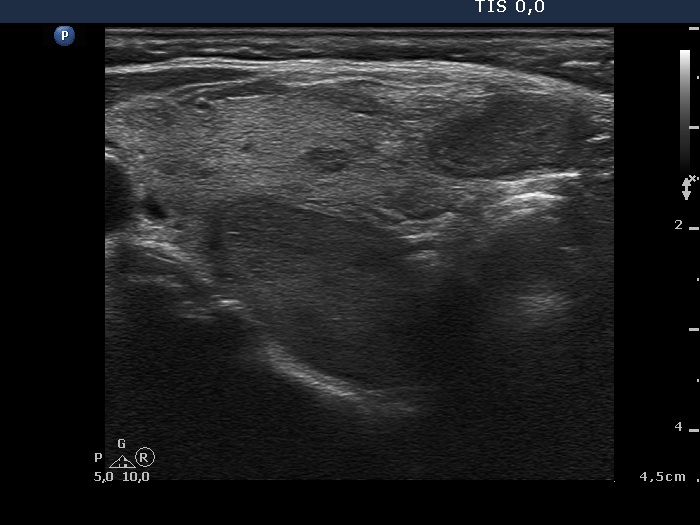

Differentiation of a parathyroid lesion from a thyroid nodule

The ultrasound differentiation of a parathyroid lesion located in the surface of the thyroid from a thyroid nodule is generally not possible. The location of the masses presented here are similar. The only important difference is that the thyroid contains another nodule with identical echogenicity in the event of hyperplastic nodule case.